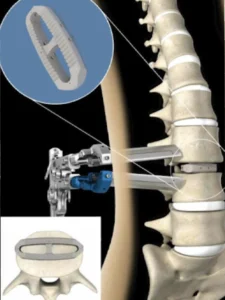

3. LLIF (Artrodese Lombar Lateral)

Também conhecida como cirurgia de acesso lateral ou pelo flanco.

- Como funciona: O cirurgião chega à coluna através do lado do corpo.

- Vantagem: É uma técnica minimamente invasiva que evita cortar os músculos principais das costas e não exige a manipulação direta dos grandes vasos ou dos nervos dentro do canal vertebral.